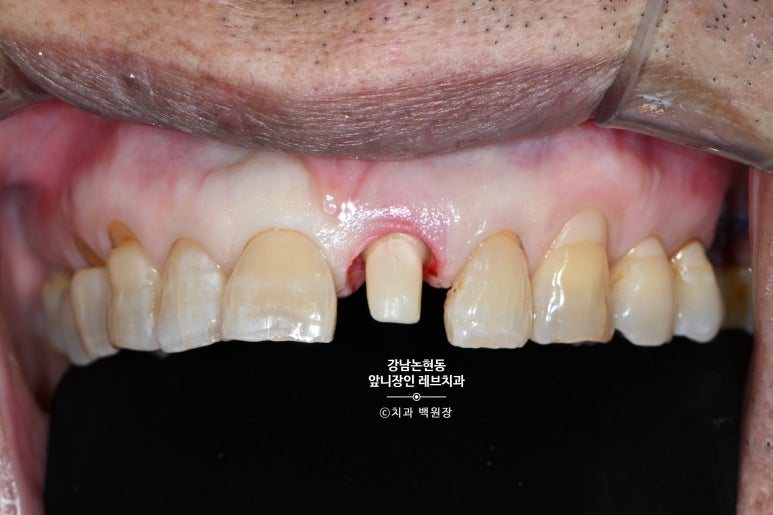

Before & After

마지막은 왼쪽 위 가운데 앞니의 치료 전과 치료 후 사진으로 마무리 해보겠습니다.

그래서 이렇게 홀수.. 특히 1개의 보철물을 치료하는 케이스가 제일 어렵습니다.

크라운 하나 빼고는 모두 자연치인 환경에서, 적절히 자연스럽게 하는건.. 예술작품을 하나 만들어내는 것과 같죠.

특히나 이번 환자분의 경우엔, 60대 나이를 가진 분으로

치아 고유의 마모도 심했고, 색상도 독특하며 옅은 가로줄무늬까지 있었습니다.

어렵게 하는 조건이 겹치면서 난이도 급상승 !!!

오히려 그냥 하얗게, 예쁘게 만드는 것을 더 쉬운 치료로 만들어버리는 그런 치료였습니다-